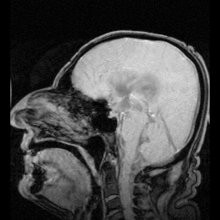

MRI showing flow of CSF

The cerebrospinal fluid passes out through arachnoid villi into the venous sinuses of the skull.